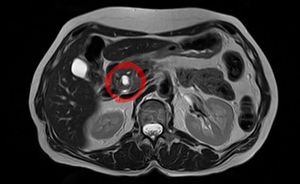

ورم مخاطي حليمي داخل قناة الپنكرياس يظهر في تصوير بالرنين المغناطيسي.